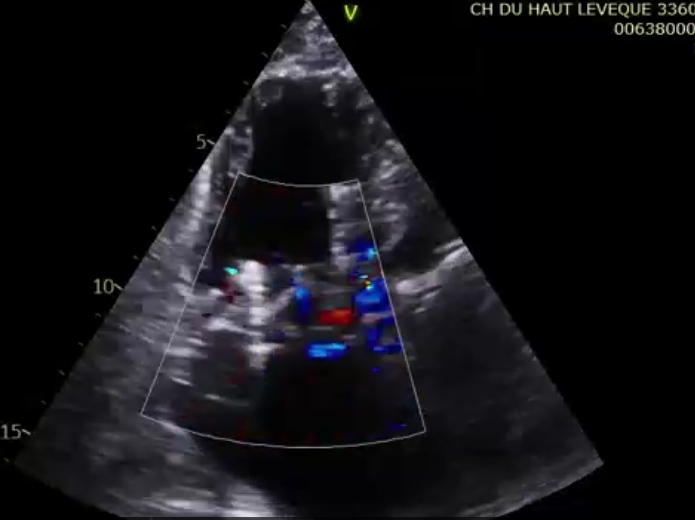

術前超聲提示極大量三尖瓣反流

第一名患者是一位83歲的女性,術前TTE診斷TR等級4+,既往有高血壓和持續性房顫的病史。術者通過右頸靜脈入路的方式將輸送系統送入右心房,在DSA和TEE的引導下對輸送系統進行調彎和推送,將輸送系統送至右心室目標位置,接著調整其同軸性,使輸送系統在多個超聲引導平面下都垂直于三尖瓣瓣環。隨后開始釋放主體支架,錨定片與夾持件放出后,在TTE的引導下確認了兩個夾持件分別在三尖瓣前葉和后葉的瓣下,且支架整體深度合適后,術者完整地釋放出整體支架。術者在DSA和TEE引導下確認了錨定片完美貼合室間隔,再次確認了瓣膜位置與同軸性良好后,通過獨有的錨定針將錨定片與室間隔固定,接著將瓣膜與輸送系統解離,完成手術。術后即刻瓣膜形態穩定,輕微反流殘留,反流下降2+以上。患者術后七天復查,經胸超聲檢查提示患者右心功能明顯改善,僅可見輕微反流。